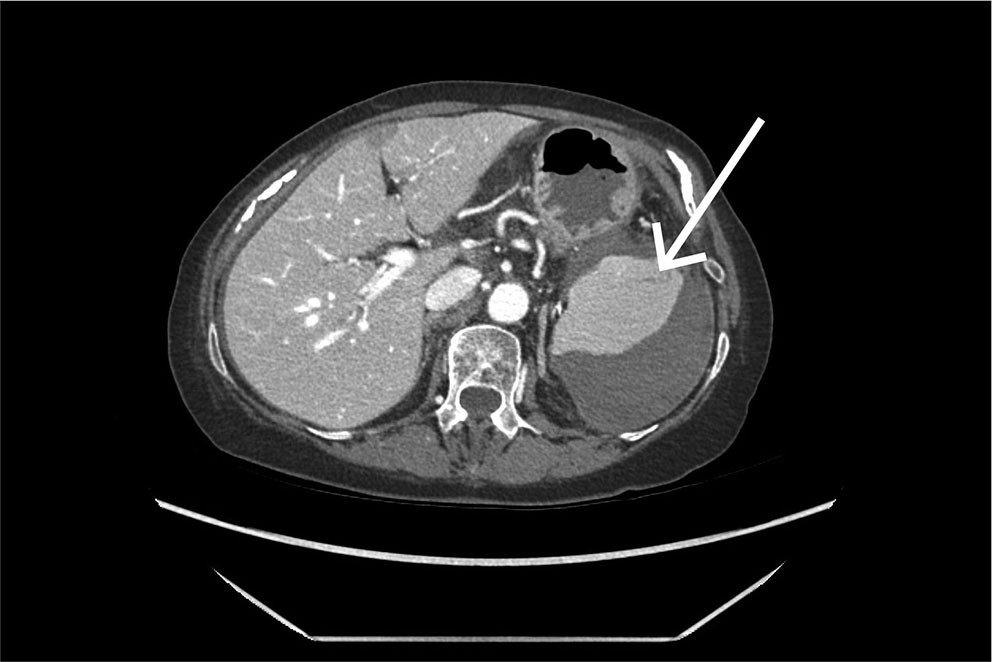

Det ble tatt CT av abdomen og bekken med intravenøs kontrast i portovenøs fase som øyeblikkelig hjelp. Undersøkelsen viste et stort, subkapsulært milthematom og en liten miltlaserasjon (figur 1). Man konkluderte med sannsynlig kapselruptur med blødning ut i fri bukhule, med væskeansamling perihepatisk, parakolisk og i det lille bekkenet. Ved regranskning av CT-undersøkelsen tatt like etter koloskopi kan man ved nærmere ettersyn se en liten subkapsulær miltlaserasjon i området for feste av ligamentum splenocolicum (figur 2).